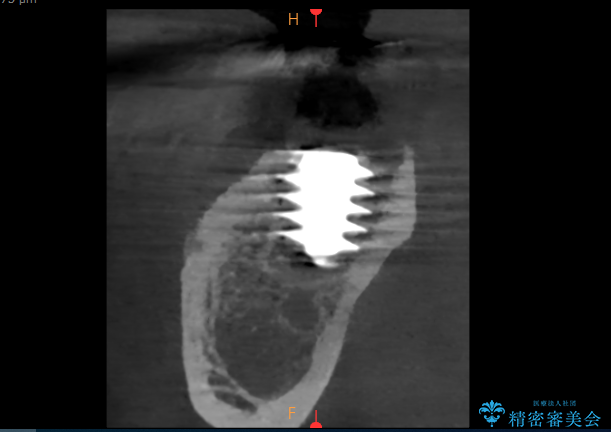

- 過去にヘミセクションが行われていたと思われる左下7番は、大きな歯根嚢胞および根尖病変が認められ、さらに骨縁下カリエスを伴っており、歯肉には瘻孔が形成されている状態でした。

保存は困難と判断し、左下7番は抜歯即時インプラントによる治療を行いました。